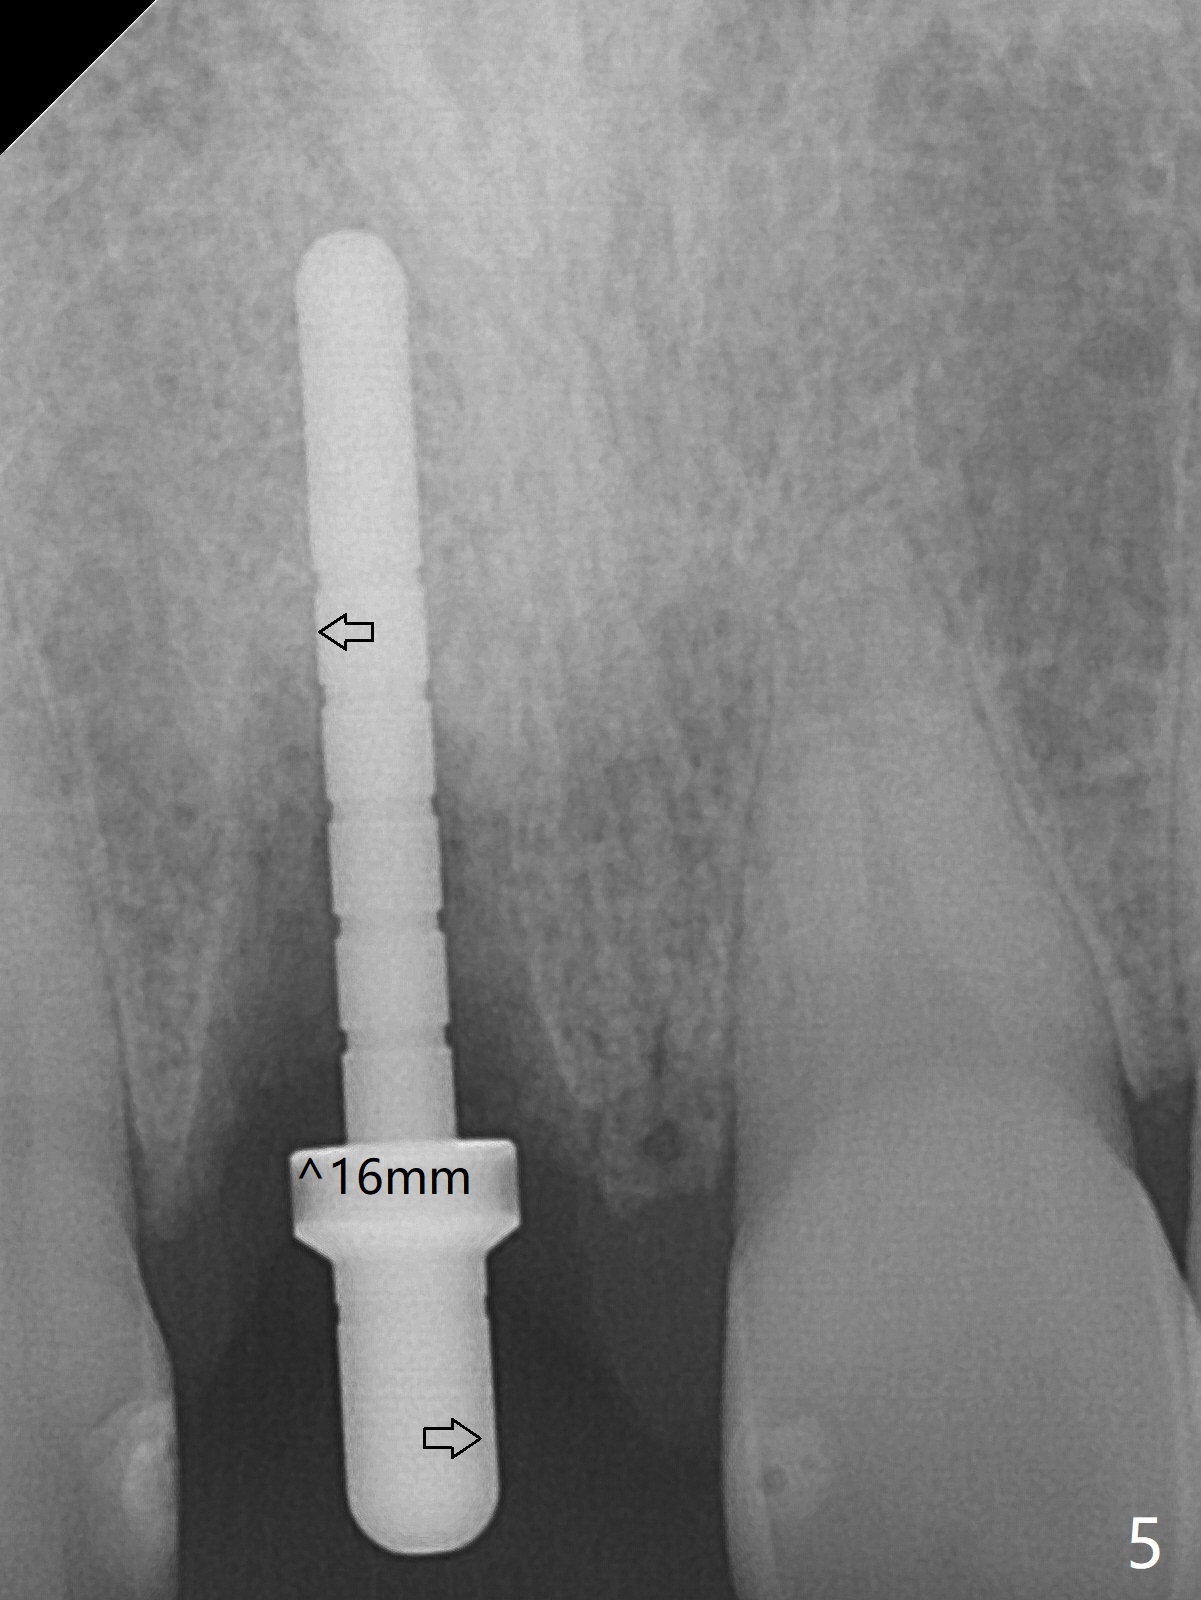

The buccal gingiva at #8 is erythematous (Fig.1: *), which is associated with the tooth fracture line (Fig.2 with granulation tissue: *). The buccal plate remains intact. Osteotomy is initiated in the palatal wall of the socket (Fig.3,4). The initial osteotomy depth is 16 mm (Fig.5); the trajectory is going to be adjusted as shown by arrows. The trajectory improves when a 3.8x15 mm dummy implant is placed (Fig.6). The definitive implant (3.8x16 mm) appears to be placed at an appropriate level (Fig.7). A 4.5x3 mm temporary abutment is inserted for an immediate provisional. As routine, Vera Graft is placed in the buccal gap. The buccal gingival erythema reduces without tenderness 1 week postop (Fig.8). Although the provisional is unstable, there is no bone loss 2 months 20 days postop (Fig.9). Because of the loose provisional (partial detachment from the underlying temporary abutment), impression is taken earlier (3 months postop, Fig.10,11). Due to the pointed abutment tip, the crown is redone 3 times. By the time of cementation (nearly 5 months postop), the socket appears to have healed (Fig.12).